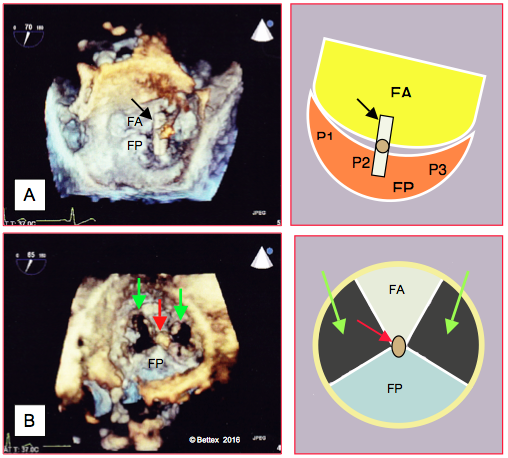

La position verticale maintenue par des compresses et par le stabilisateur de l'anastomose a pour effet de plier le cœur au niveau du sillon auriculo-ventriculaire et de provoquer une distorsion de l'anneau mitral et de l'anneau tricuspidien. L'anneau est déformé à telle enseigne que la valve fuit; une IM modérée-à-sévère se développe chez environ 60% des malades pendant ces manoeuvres (Vidéo) [4]. L’apparition d’une IM sévère est plus fréquente chez les malades qui souffrent déjà d’une régurgitation mitrale modérée. La reconstruction tridimensionnelle montre que le déplacement mécanique du cœur tord l'anneau mitral, particulièrement lors d'anastomose sur la face latérale (artère circonflexe) [4]. Avec une ventouse qui suspend le VG par l'apex, la déformation de l'anneau mitral est moins brutale, mais il perd sa forme en selle lors des anastomoses sur la circonflexe et sur la coronaire droite (IVP), ce qui aggrave l'IM (voir Figure 10.6) [17].

Figure 10.6 : Modifications de la forme de l'anneau mitral reconstruit en 3 dimensions à partir d'images ETO. A. Forme normale en selle de l'anneau mitral lorsque le coeur est dans sa position normale. B: L'anneau est tordu lorsque le coeur est dressé verticalement. C: L'anneau est replié sur lui-même lorsque le coeur est placé en position pour une anastomose sur la face latérale [4]. D: Forme en selle normale; la double flèche rouge indique la hauteur de l'anneau (environ 7 mm); Ao: valve aortique. E: L'anneau est aplati lors d'anastomose sur l’artère circonflexe. F: Il en est de même lors d'anastomose sur la face postérieure (IVP) [d'après: Toyama Y, et al. Morphologic evaluation of the mitral annulus during displacement of the heart in off-pump coronary artery bypass surgery. J Cardiothorac Vasc Anesth 2018; 32:334-40].